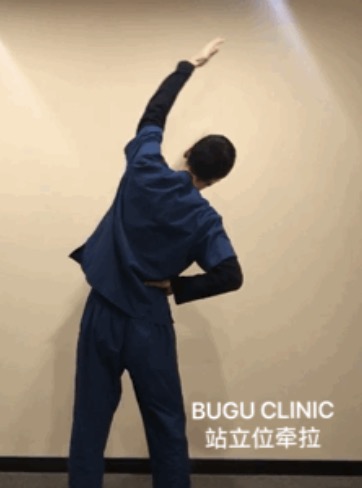

- 脊柱功能性疼痛是怎么回事?治疗方案是什么? 布骨康复医疗中心 ,2020-02-03

- 脊柱的最长部分,脊背主要负责保护脊髓。虽然它是由肋骨支撑的,但它仍然可能是疼痛和不适的部位。在电脑前工作常常是问题的原因! 背或胸椎有12节椎骨,从最后一节颈椎到第一节腰椎,呈自然弯曲,称为后凸。它的作用是支撑身体和保护脊髓。肋骨与背脊骨相连。 .....

- 脊柱是我们身体的中心支柱,如果出现背痛,解决方案是什么? 布骨康复医疗中心 ,2020-02-02

- 脊柱,也被称为脊柱或脊椎骨,是我们身体的中心支柱。 它的主要作用之一是引导躯干允许我们做的许多动作:弯曲、伸展、旋转、倾斜。它由24个椎骨组成:7个颈椎骨,12个胸椎骨和5个腰椎椎骨,5个骶骨椎骨和3 - 5个尾骨椎骨。像所有的关节一样,椎骨是由许多韧带和肌肉连接在一起的。它们由一个椎间盘隔开,椎.....